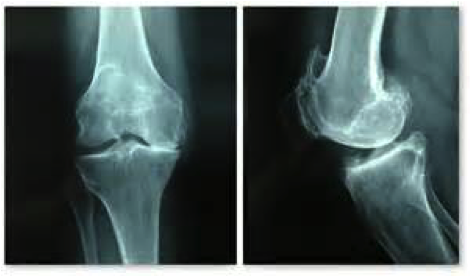

Risque à long terme

C’est en effet le risque d’arthrose. La répétition des accidents d’instabilité, surtout si les ménisques, véritables amortisseurs, sont également déchirés, peut entraîner cette usure du cartilage du fémur et du tibia qui représente l’arthrose du genou.

Elle peut devenir responsable de douleurs persistantes, et d’épanchements à répétition.

Le traitement d’une telle arthrose peut être difficile en raison de sa survenue chez des sujets souvent encore jeunes…